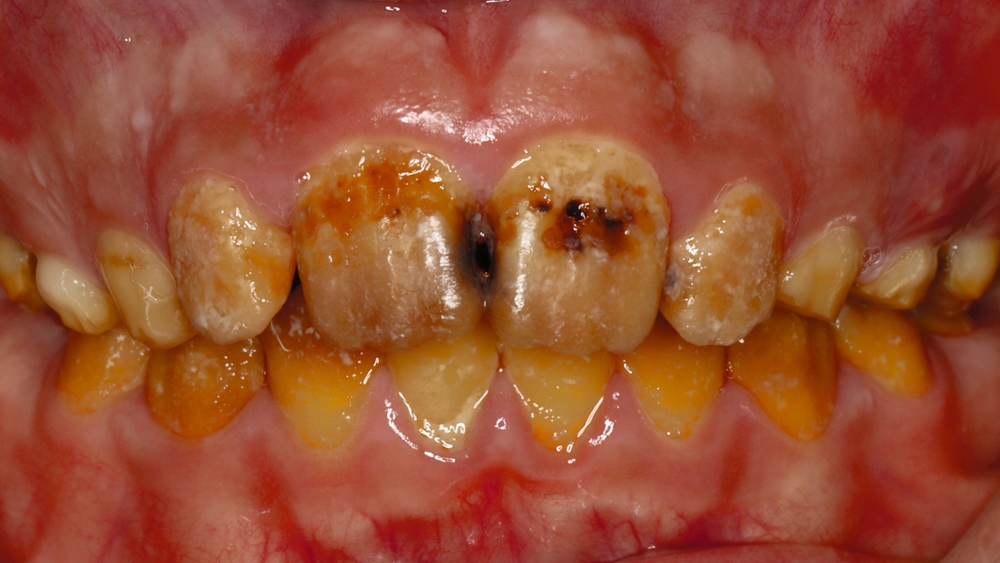

Klinisch zeigte sich ein kariöses Wechselgebiss mit generalisierten Verfärbungen und rauer Schmelzoberfläche. Mehrere Milch- und bleibende Zähne wiesen aktive kariöse Läsionen auf. Zahn 64 war zusätzlich druckdolent und gelockert, mit einer vestibulären Schwellung der Gingiva. Zudem bestanden eine Mittellinienabweichung, ein Overbite von vier Millimetern und ein Overjet von elf Millimetern (Abbildung 1). Extraoral fiel ein fliehendes Kinn mit inkomplettem Lippenschluss und hyperaktivem Musculus mentalis auf. Röntgenologisch waren alle Zähne angelegt, der Zahnschmelz zeigte jedoch eine reduzierte Opazität (Abbildung 2). Eine genetische Abklärung wurde von den Erziehungsberechtigten aus ethischen Gründen abgelehnt.

Auf Grundlage des klinischen und des radiologischen Befunds wurde die Verdachtsdiagnose einer isolierten AI gestellt und als hypomineralisierter Typ klassifiziert [Witkop, 1988]. Differenzialdiagnosen wie eine Fluorose oder syndromale Formen konnten ausgeschlossen werden.

Nach der Extraktion von Zahn 64 wurden die übrigen kariösen Milchzähne nach Konditionierung (Prime&Bond NT, Dentsply Sirona) mit Kompomer (Dyract extra, Dentsply Sirona) versorgt. Für die Frontzahnbehandlung wurde zunächst ein Wax-up auf Situationsmodellen erstellt (Abbildung 3), anschließend eine Silikonformhilfe angefertigt. Nach Reinigung und 3-Schritt-Etch-and-Rinse-Konditionierung (OptiBond FL, Kerr) unter relativer Trockenlegung wurden die Zähne in Mehrschichttechnik mit einem Mikrohybrid-Komposit (Herculite XRV, Kerr) versorgt. Die Seitenzähne wurden wegen des ausgeprägten Würgereizes unter absoluter Trockenlegung mit fließfähigem Komposit (Tetric flow, Ivoclar Vivadent) temporär rekonstruiert (Abbildung 4).